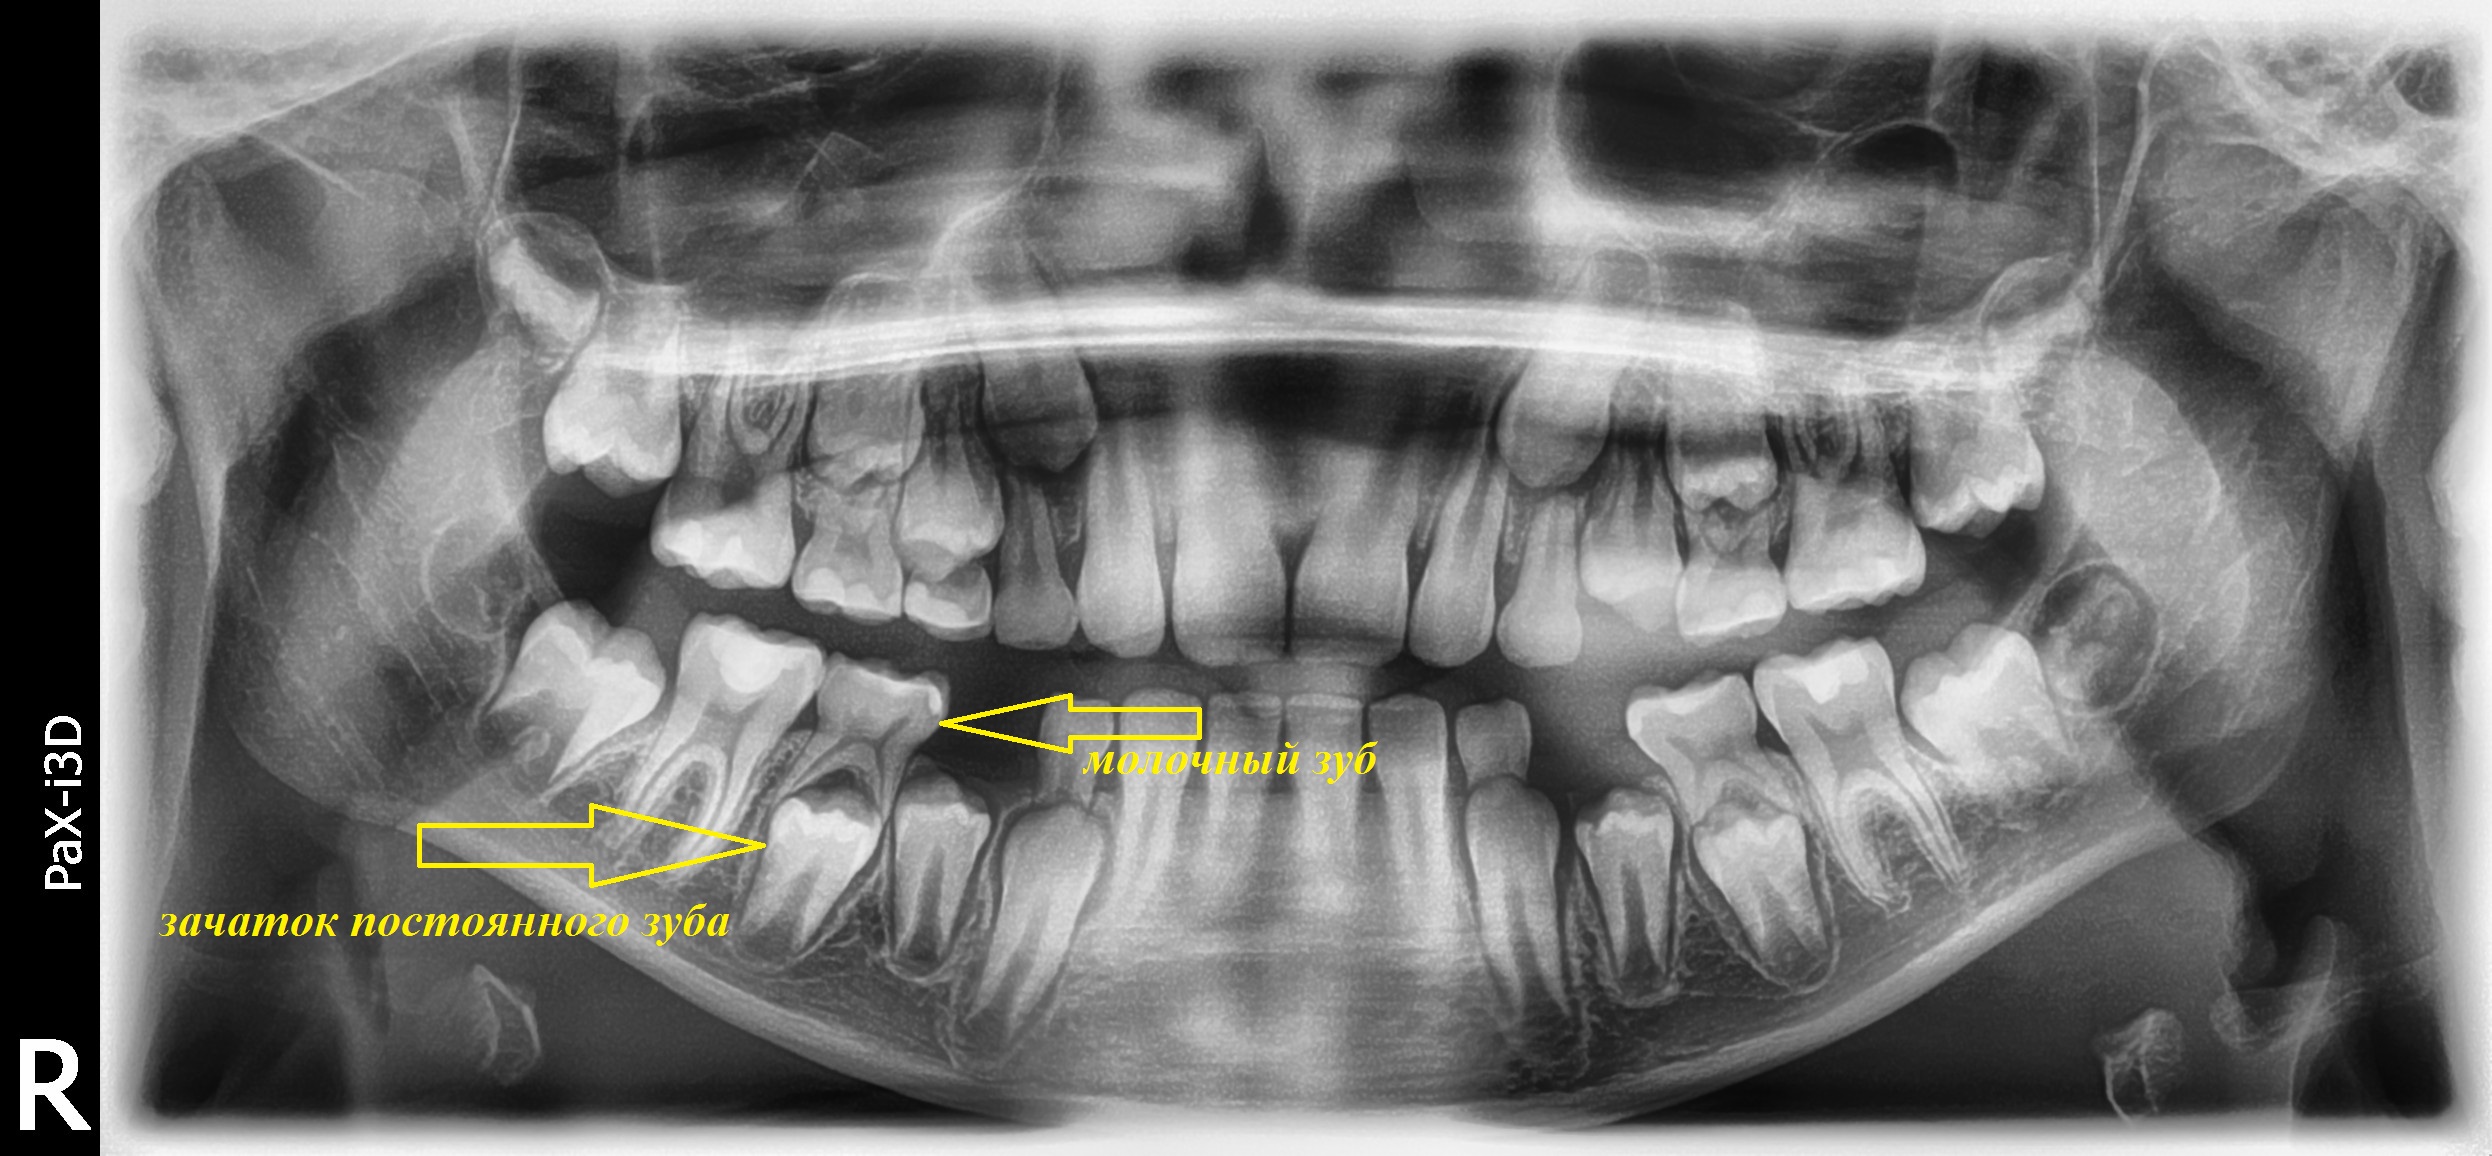

Стоматологические Исследования: Рентген Инвагинации Зубов